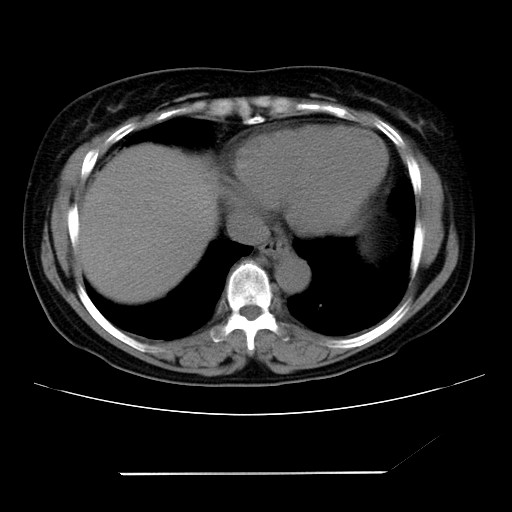

女性,62岁,长期咳嗽,既往从事工作有粉尘接触,有高血压病史,110/150mmhg,近日咳嗽加重,脸面浮肿,请大家帮看下,

慢支并肺部炎症;右肺结核球?主肺动脉、右肺动脉影不宽,右心室不大,不支持肺心病;无心包积液。

右肺无结核球,是肝上缘